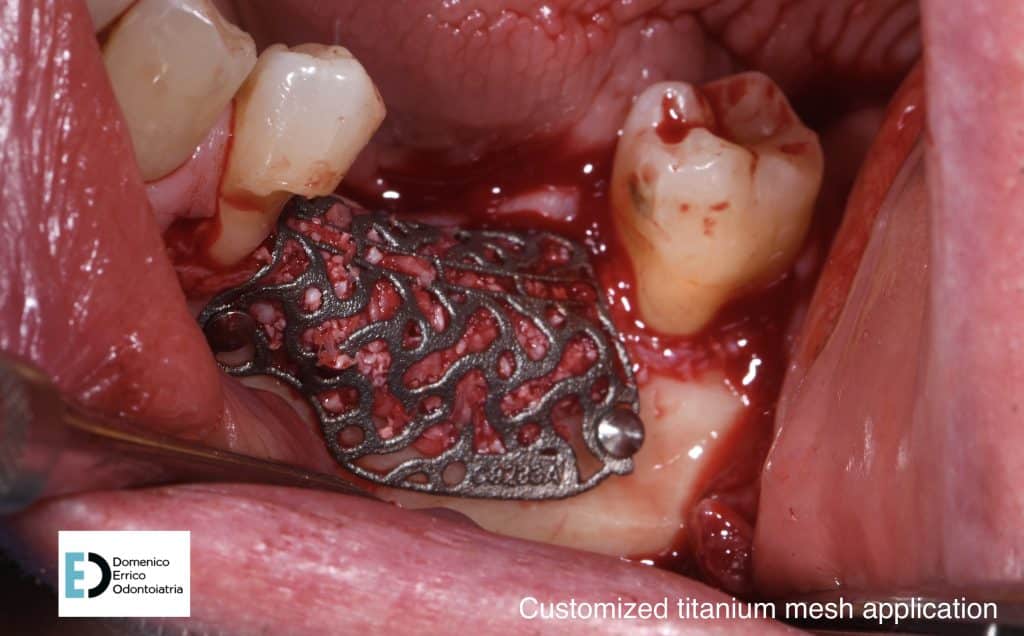

The treatment objectives are primarily functional: the restoration of volumes, necessary for implant rehabilitation due to insufficient bone height for fixture placement applying a mesh with a filler, consisting of 50% autologous bone and 50% heterologous bone; the reinstatement of chewing function by a second intervention to remove the mesh and simultaneously place two implant fixtures, concurrent with an increase of adherent gingival tissue level; and finally, the goal is to achieve the correct vertical relationship between the upper and lower arches through prosthetic rehabilitation of the upper arch with the replacement of the old prosthetic device.

– “Customized 3D-Printed Titanium Mesh Developed for an Aesthetic Zone to Regenerate a Complex Bone Defect Resulting after a Deficient Odontectomy: A Case Report” Gabriela Luminița Gelețu, Alexandru Burlacu, Alice Murariu, Sorin Andrian, Loredana Golovcencu, Elena-Raluca Baciu, George Maftei and Neculai Onica